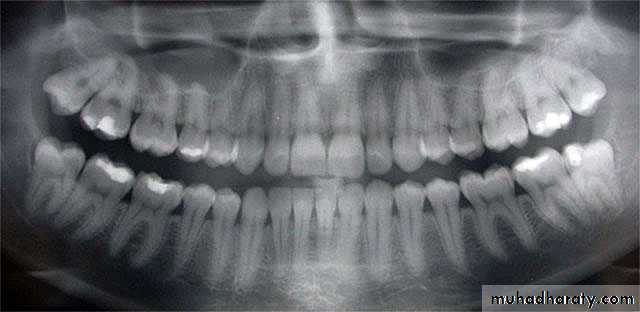

• -Panorex radiographs for evaluation of mandible.

Panorex film